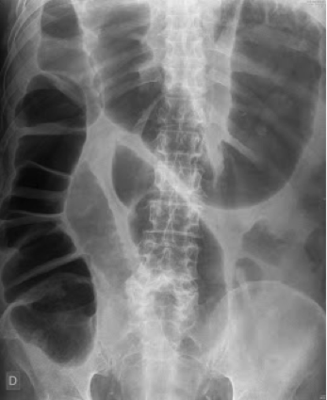

Paciente masculino 70 años con adicción a narcóticos, acude a urgencias por constipación grave y distensión abdominal. No presenta datos de irritación peritoneal y se encuentra deshidratado. Se realiza rx abdominal simple: ¿Cuál es el diagnóstico de este paciente?

Answer

• Colitis isquémica.

• Colitis pseudomembranosa.

• Vólvulo sigmoideo.

• Síndrome de Ogilvie.